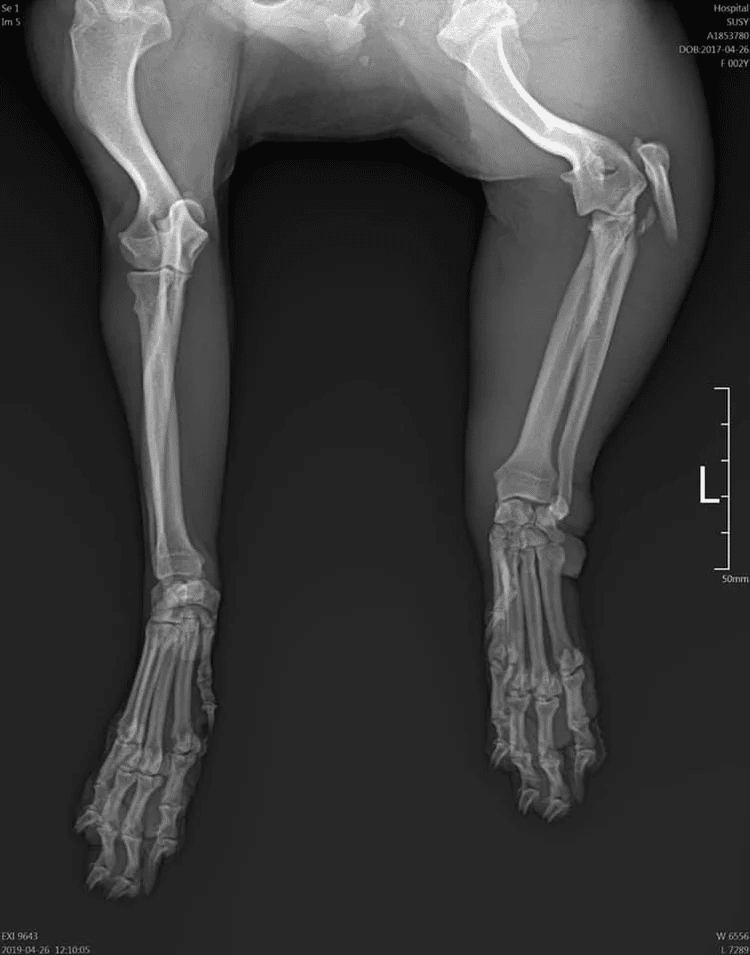

Suzy

Breed: Spaniel mix